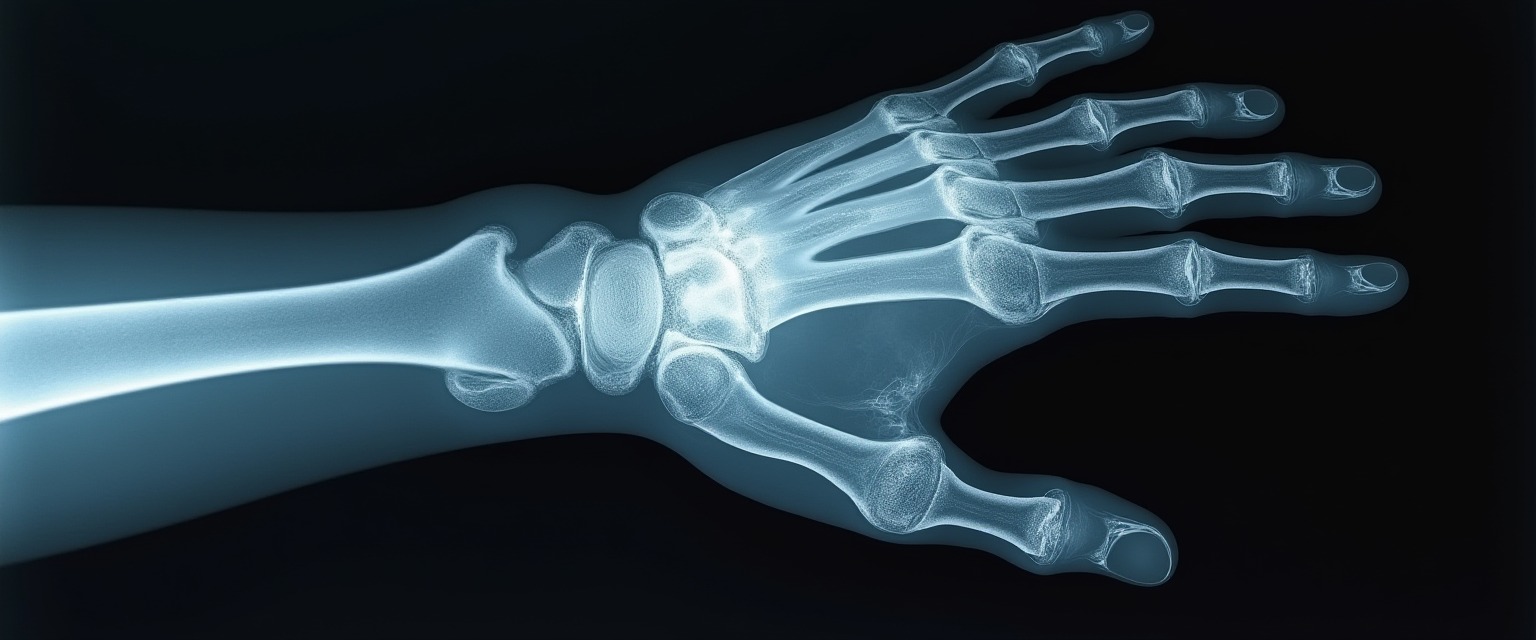

Функциональная работа кистей рук очень важна для многих профессий, особенно для хирургов.

Случай из практики Полины Михалакисовны Кириаку, травматолога-ортопеда, руководителя направления кистевой терапии клиники «Семейная»

Пациент обратился к Гайку Кареновичу с жалобой на боль и ограничение подвижности в лучезапястном суставе

К нашему опытному неврологу Ойбеку Тургунхужаеву обратился мужчина 27 лет с жалобами на ночные боли в левой кисти